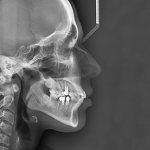

К дополнительным средствам относятся различные функциональные пробы, исследование диагностических гипсовых моделей челюстей, трансверсальные, сагиттальные и вертикальные измерения, рентгенография, томография.

Очень информативной является рентгеноскопия, особенно, телерентгенография, дающая фронтальные и боковые снимки лица, позволяющие оценить взаимоположение челюстей.

Полезную общую информацию дает ортопантомография, по которой можно также установить объем носовых пазух.